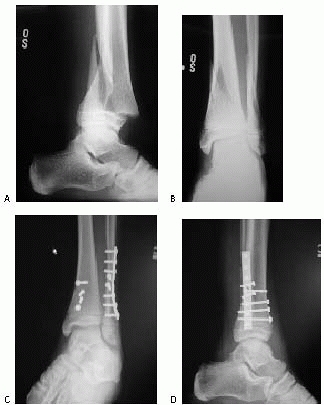

FIGURE 26-35 A.

Severe ankle injury sustained by an 8-year-old involved in a car accident. The anteroposterior view in the splint does not clearly show the Salter-Harris type IV fracture of the tibia. The dome of the talus appears abnormal. B. CT scan shows the displaced Salter-Harris type IV fracture of the medial malleolus and a severe displaced intra-articular fracture of the body of the talus. C,D. Open reduction of both fractures was performed, and Herbert screws were used for internal fixation. (Courtesy of Armen Kelikian, MD.) |